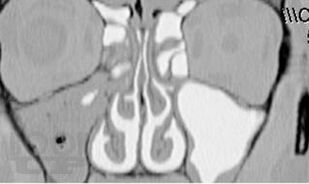

Хронический риносинусит

Представлены данные об этиологии, патогенезе, классификации форм хронического синусита. Приведен обзор современных методов диагностики и лечения. Обсуждается консервативное лечение синуситов с учетом особенностей микрофлоры, освещены не только стандартные хирургические подходы, но и некоторые базовые и прикладные вопросы функциональной эндоскопической риносинусохирургии.